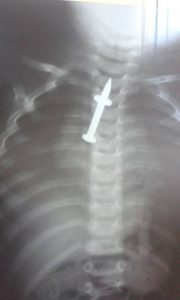

გადაცემა „ექიმების“ წამყვანი ფეისბუქის საკუთარ გვერდზე ბავშვის რენტგენის სურათს აქვეყნებს, სადაც ნათლად ჩანს, თუ რა გადაყლაპა მოზარდმა.

“ერთი წლის ბავშვის საყლაპავში შეიძლება აი, ასეთი რამეც კი აღმოჩნდეს…”- წერს ლევან ხარაშვილი სოციალურ ქსელში.